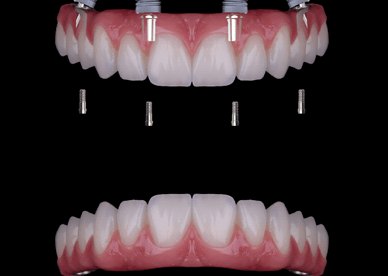

Como hemos hablado en varios post anteriores, un implante dental es una solución fija para reemplazar un diente perdido. Un implante cementado significa que la corona cerámica (el diente visible) está permanentemente unida al pilar del implante con cemento dental. Esto crea una apariencia natural y continua (sin agujeros visibles de tornillo) y una […]